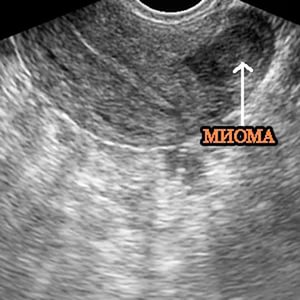

- УЗИ – наиболее информативный метод из доступных, и часто назначаемый;

Шеечная миома матки диагностируется гораздо проще, чем остальные типы таких новообразований. Хотя она, как и большинство других типов миом, протекает бессимптомно. Однако за счет ее относительно не скрытого расположения, она порой может быть диагностирована случайно. Например, в ходе планового гинекологического осмотра, даже без УЗИ. В общем случае для постановки диагноза используются следующие методы: